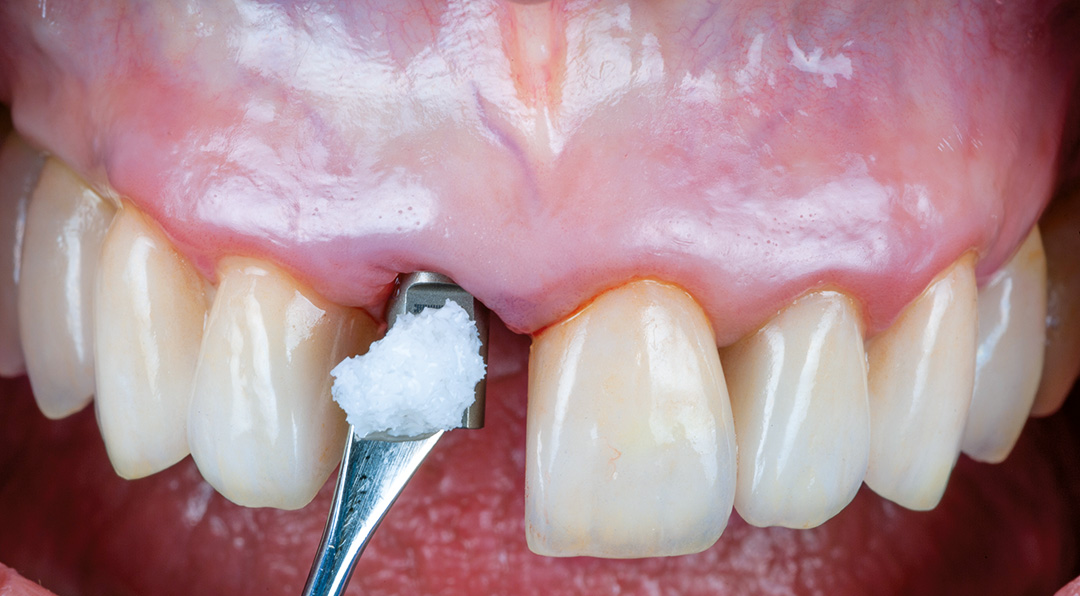

A minimally invasive extraction was performed using the Benex® system to preserve the thin buccal bone. A 3.3 x 11 mm CONELOG PROGRESSIVE-LINE implant was placed using a fully guided protocol. Despite the narrow implant diameter, a torque of 20 Ncm was achieved, facilitated by good palatal bone availability, under-preparation of the osteotomy and the macro design of the implant. The peri-implant gap was grafted with MinerOss X, chosen for its slow resorption profile and volume-stabilising characteristics. A connective tissue graft was harvested from the tuberosity by performing a distal wedge in the region of tooth 1.8. The graft was secured in a buccal pouch using a horizontal mattress suture with 6-0 polypropylene to support the emergence profile and soft tissue volume. A customised healing abutment was placed to seal the socket and guide soft tissue healing. A provisional resin-bonded restoration was applied out of occlusion.

The chosen treatment approach provided several clinical advantages. The fully guided protocol using coDiagnostiX software allowed for precise and minimally invasive implant placement, which was particularly beneficial given the thin buccal bone anatomy. Grafting with MinerOss X helped to maintain buccal contour and support volume stability in the thin periodontal phenotype. Using a connective tissue graft harvested from the tuberosity further enhanced soft tissue thickness and it was placed with minimal trauma using horizontal mattress sutures for secure adaptation. A customised healing abutment and staged provisionalisation supported controlled soft tissue maturation during healing. Finally, the restoration was completed with a screw-retained ceramic crown on a customised anodised titanium abutment, providing long-term stability and a highly aesthetic result.